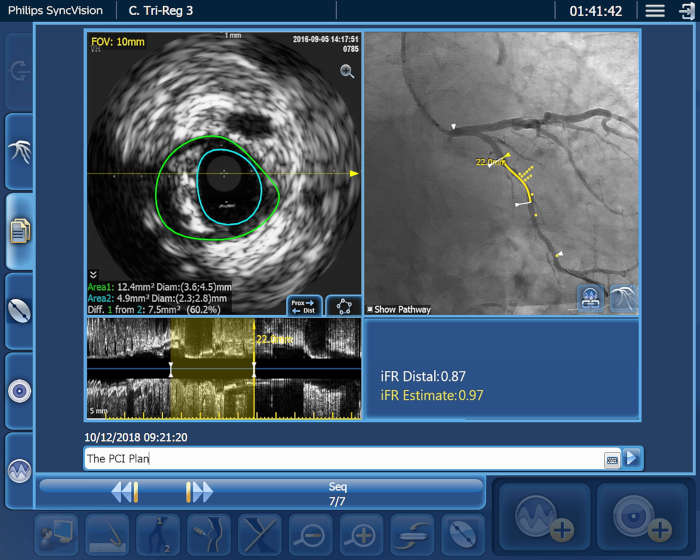

A medida que aumenta el número de pacientes cardiovasculares y vasculares, también lo hace la necesidad de trabajar de forma más inteligente y rápida. Philips IntraSight le ofrece estas herramientas intervencionistas, las mejores de su clase, que le permiten ver con claridad para poder tomar decisiones clínicas rápidas e informadas que pueden conducir a planes de tratamiento óptimos. La integración de la más avanzada plataforma de fisiología e imagenología en su flujo de trabajo debe ser inteligente, sencilla y constante. IntraSight es la única plataforma intervencionista que: Para los clientes con suites intervencionistas que no son de Philips, IntraSight 7 ofrece una integración constante y un uso completo de nuestras aplicaciones de intervención. IntraSight 7 promueve una gestión mejorada del flujo de trabajo con el módulo de pantalla táctil junto a la mesa que permite la facilidad de uso y el acceso a las mejores herramientas intervencionistas de su clase, como iFR/FFR, IVUS y el corregistro. Además, la integración de IntraSight 7 con las suites intervencionistas que no son de Philips permite a los clientes beneficiarse de soluciones intuitivas como, por ejemplo, la mejora de los vasos y la detección de dispositivos, lo que, en última instancia, permite a todos los clientes beneficiarse de la oferta integral de soluciones inteligentes de IntraSight 7 sin compromiso.

Presentamos la nueva plataforma de aplicaciones intervencionistas Philips IntraSight, en la que la imagen, la fisiología, el corregistro* y el software se unen para facilitar una atención óptima del paciente. IntraSight ofrece un conjunto completo de modalidades clínicamente probadas, como la iFR/FFR, la IVUS y el corregistro* para simplificar las intervenciones complejas, acelerar los procedimientos rutinarios y proporcionar una mejor atención al paciente.

Construida sobre una plataforma inteligente basada en aplicaciones que puede escalar para satisfacer las necesidades cambiantes de su laboratorio cuando se disponga de nuevas aplicaciones o modalidades, sin necesidad de adquirir nuevo hardware. Solo Philips IntraSight ofrece las mejores herramientas de imagenología y fisiología de su clase con iFR, corregistro iFR*, FFR, IVUS, corregistro IVUS* y Angio+*. Con su arquitectura modular, IntraSight se mantiene a la vanguardia de los últimos avances y actualizaciones de seguridad importantes.

IntraSight está perfectamente integrada

Optimización del rendimiento del laboratorio con control de pantalla táctil en la mesa, integración de sistemas, gestión de datos y diagnóstico de servicios remotos.

Aumente la eficiencia de los casos, ahorre tiempo y reduzca los errores con datos integrados

Figura 3

Figura 4